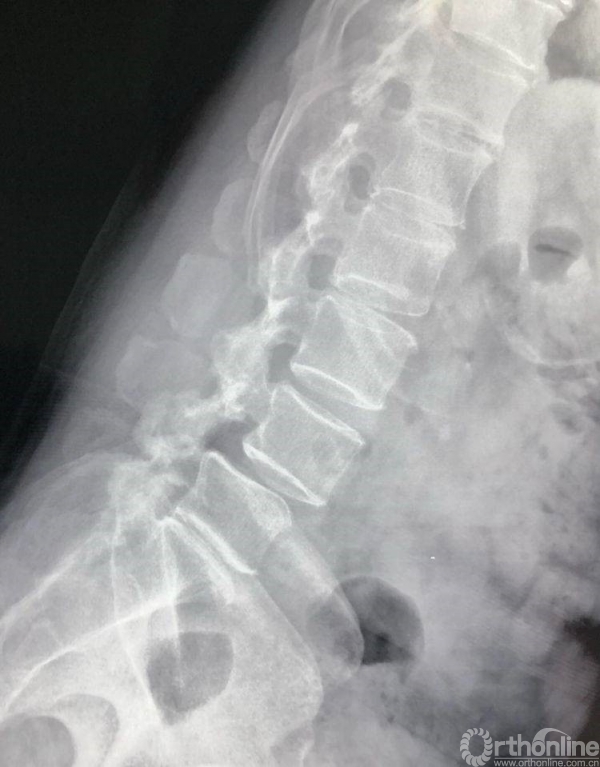

术前CT示L4/5重度椎管狭窄,腰椎滑脱合并硬膜囊受压。辅助检查如下:

过屈位X片